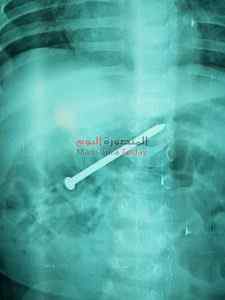

صرح الدكتور أحمد الرفاعى مدير مستشفى الأطفال بجامعة المنصورة عن تمكن فريق جراحى بوحدة الجهاز الهضمى بمستشفى الأطفال بجامعة المنصورة من اجراءعملية استخراج مسمار طوله 6 سم ، باستخدام المنظار بدون اى جرح أو مضاعفات أو تدخل جرحى من بطن طفل عمره ٩شهور .

وقامت الأم خلال ستة أيام بمحاولة استخراج المسمار طبيا ، حتى جاءت مستشفى الاطفال الساعة التاسعة صباحا ، وتم عرض الحالة على الفريق الطبى وتم إجراء الأشعة لتحديد مكان المسمار وقرر الفريق استخراجه باستخدام المنظار وتمت العملية بسلام من غير مضاعفات والطفل غادر المستشفى فى نفس اليوم .